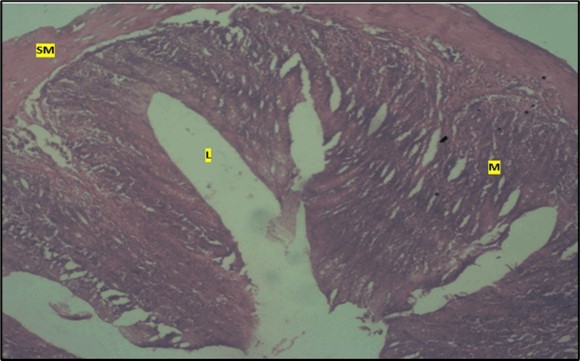

Micrographs of The Large Intestine

Results from the large intestine histological observation showed normal appearance of epithelial cells lining the mucosa with no pathological observations in control animals (Figure 5). However, administration of Abelmoschus esculentus at low dose showed dysplasia of cells and loss of normal epithelial shape (Figure 6) and the high dose group showed mild dysplasia (Figure 7)

Figure 5.Control showing the lumen (l), the epithelial cells lining the mucosa (m) appearing normal H & E. X40.

Figure 6.Low dose showing the lumen (l), smooth muscle layer (sm) and dysplasia of the mucosa (m). there is loss of epithelial shape H & E. X40.